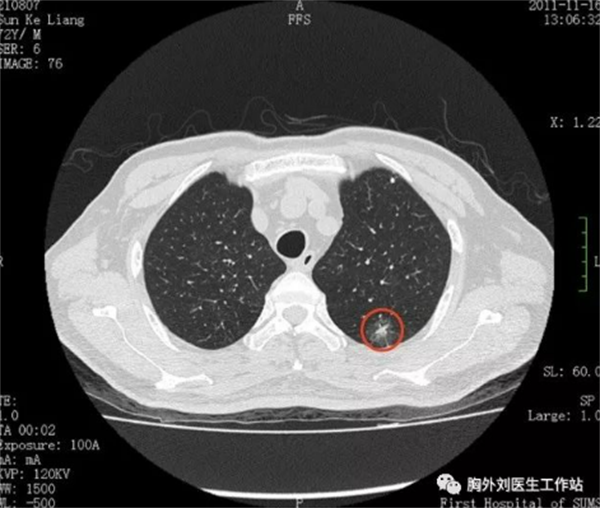

▲图为特别早期肺癌胸部CT(GGO病变)

一些特别早期的肺癌(如原位癌或影像学表现为GGO磨玻璃样病变的早期肺癌),手术根治后10年生存率可达到95%以上,甚至实现完全治愈;对于相对早期的非小细胞肺癌(NSCLC),一般手术根治后,5年生存率(活到5年的概率)约70%以上;但是对于一些恶性程度比较高的肺癌,如广泛期小细胞肺癌,或者比较晚期的NSCLC(如肺癌已经发生了局部或全身转移,如转移到脑、骨、或双肺等),预后往往很差,治疗效果往往不好,一般5年生存率低于10%。